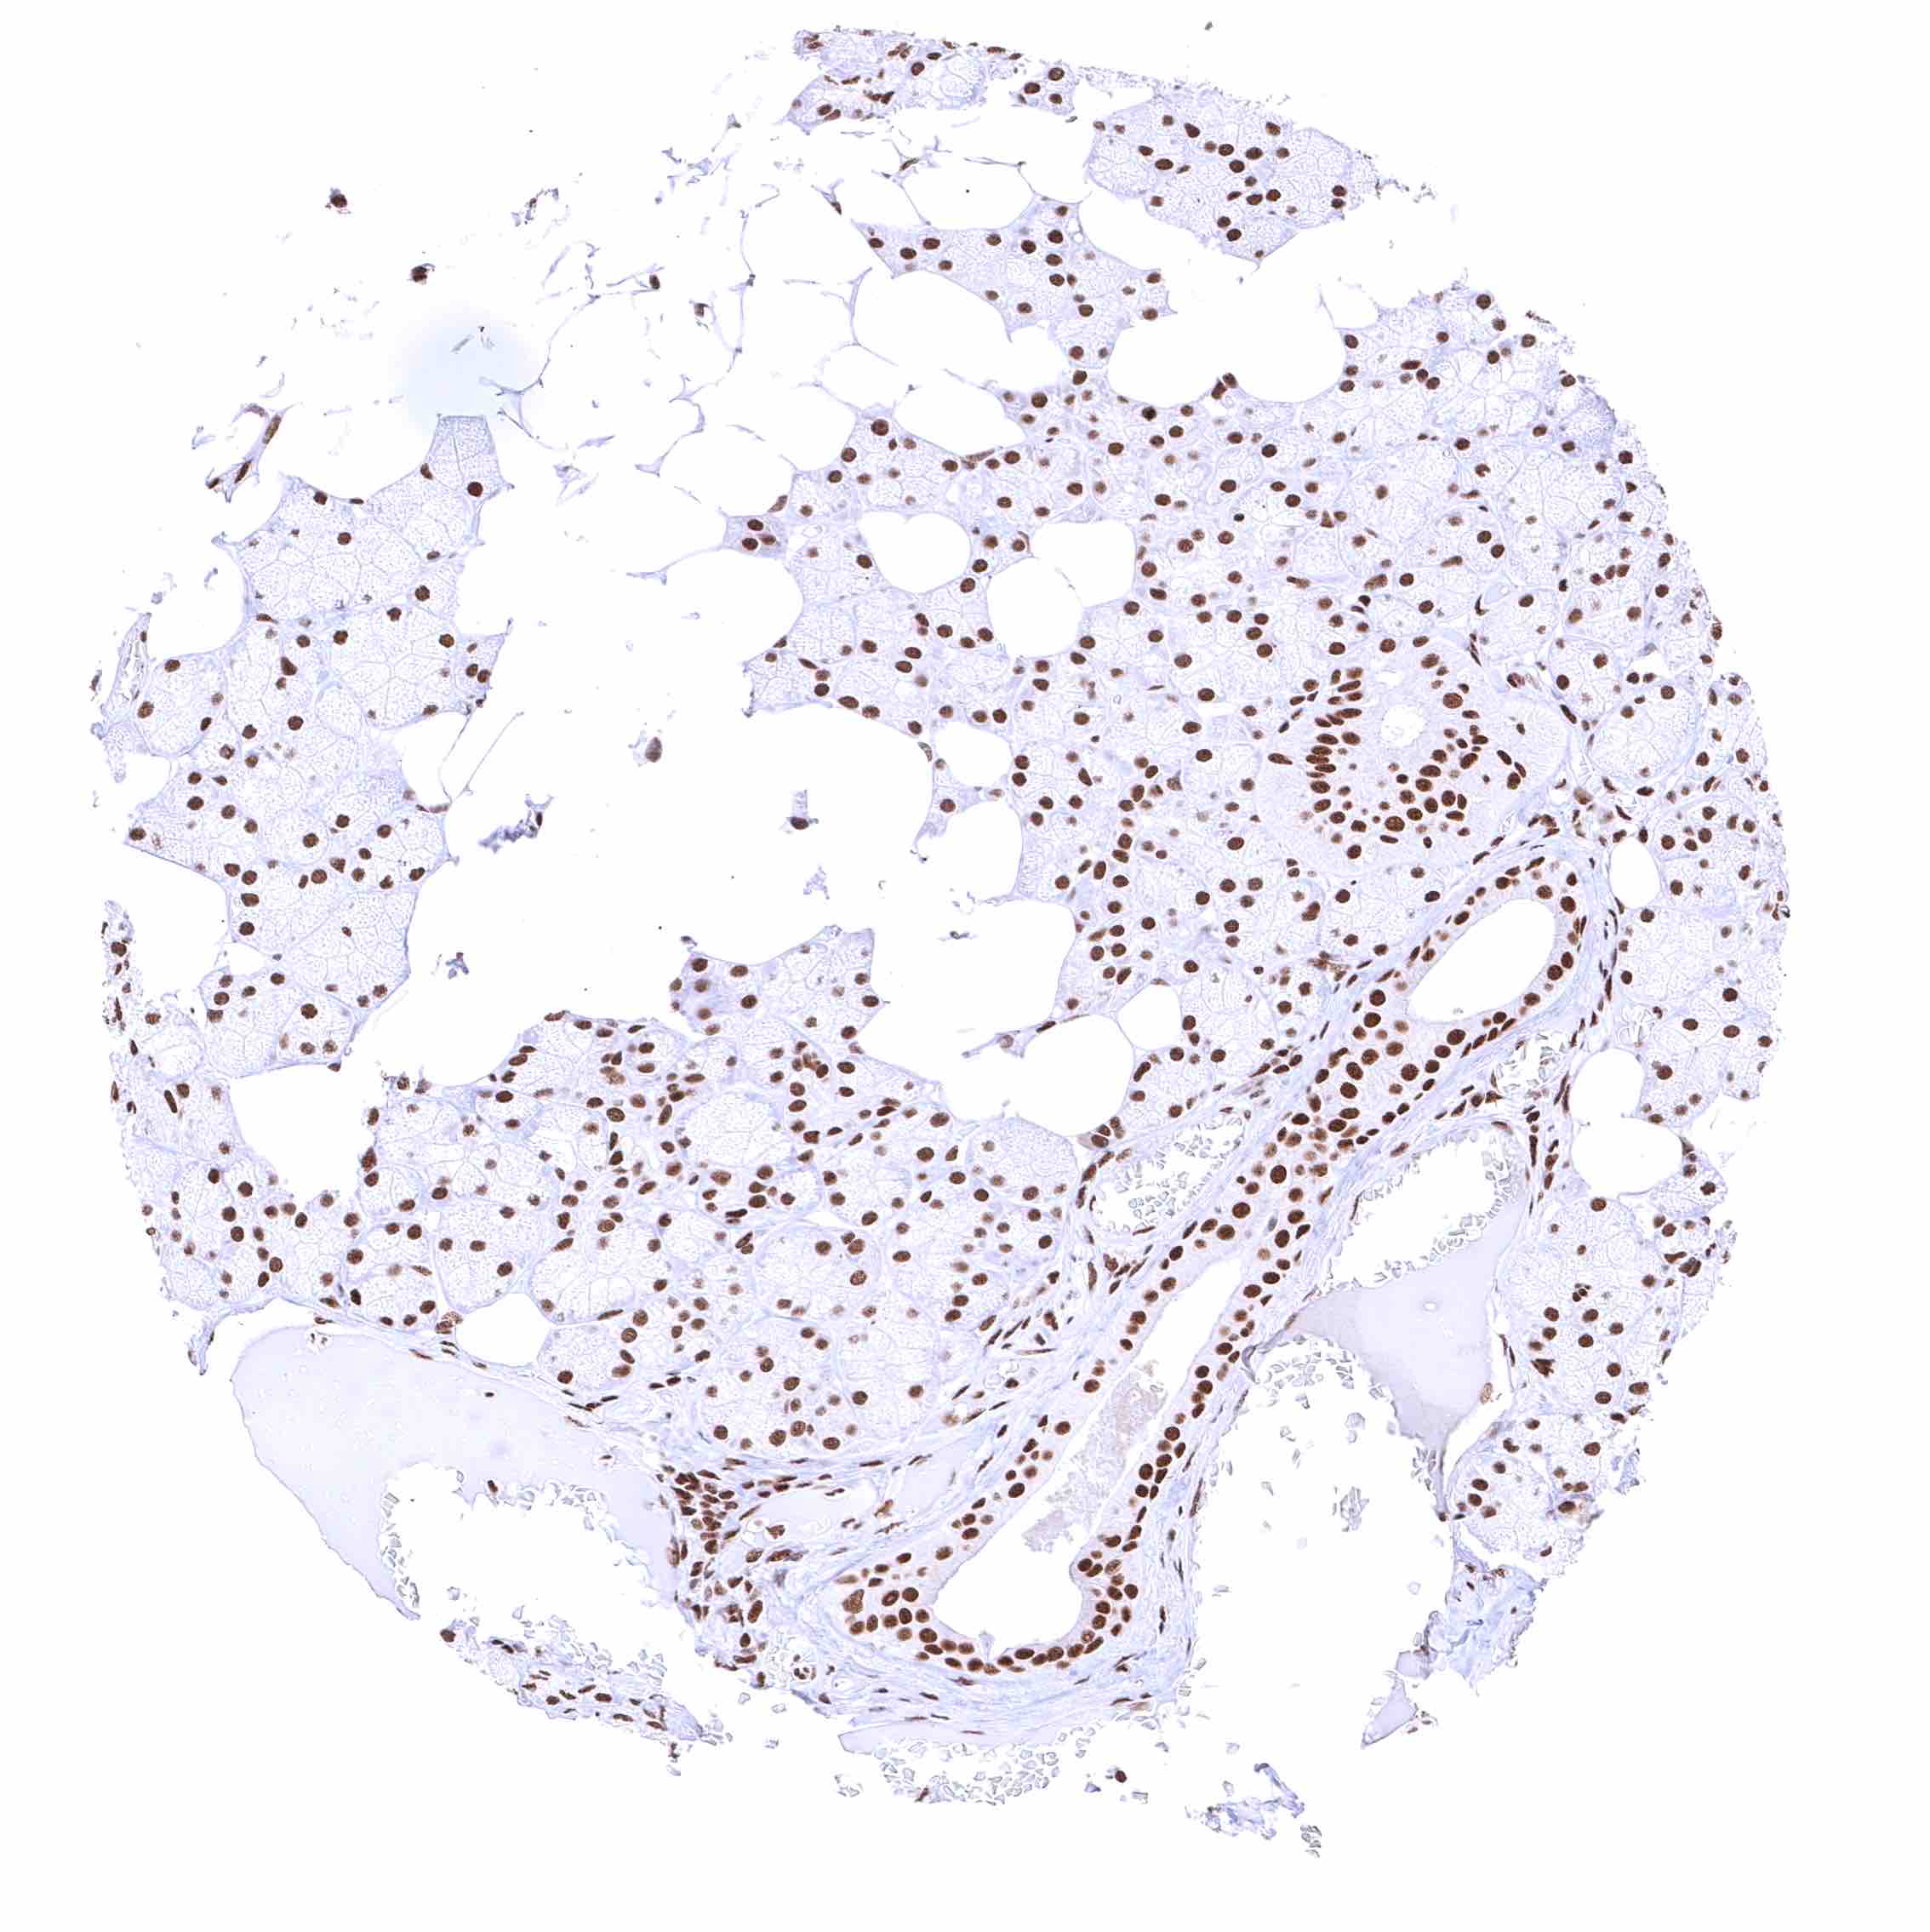

Fat – Distinct nuclear BRD4 staining of fat cells.